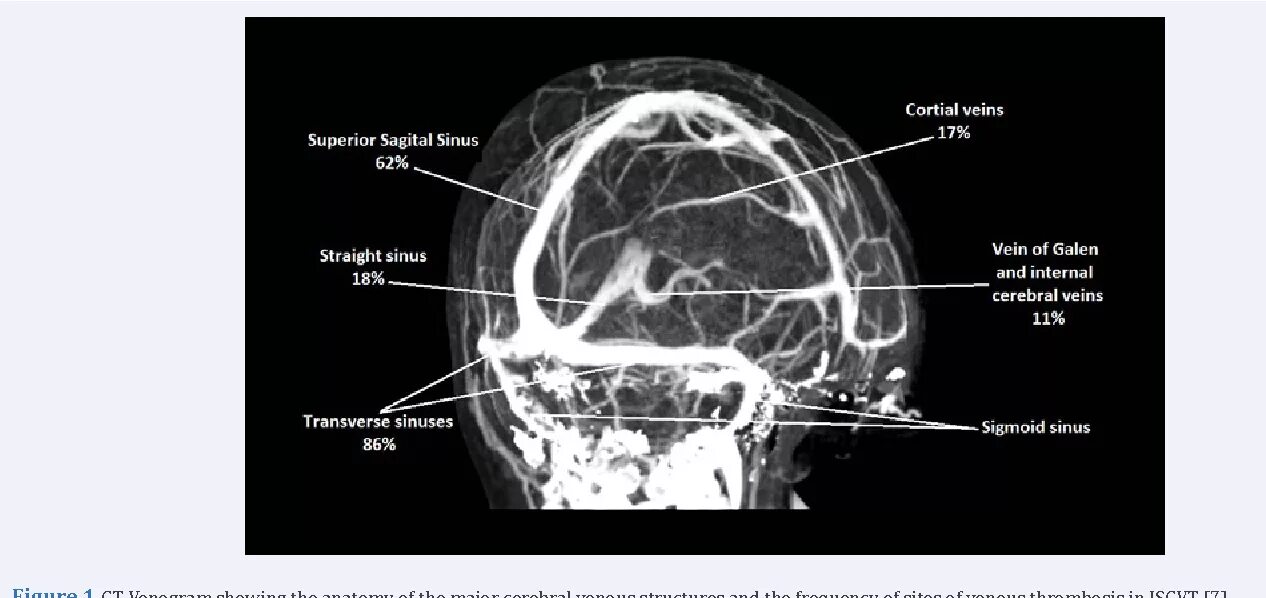

Синусы мозга мрт